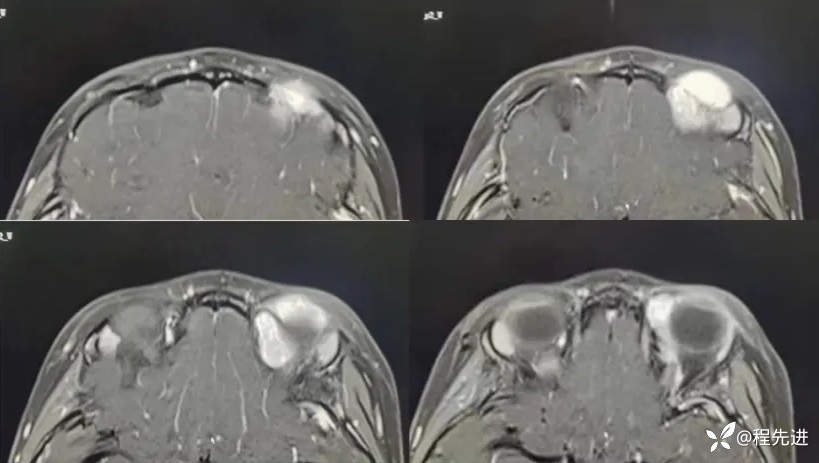

MRI平扫+增强:

T1增强: